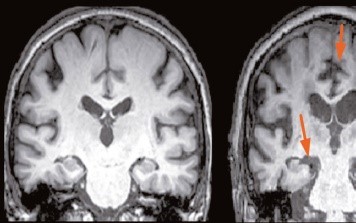

- Ο απεικονιστικός έλεγχος, όπως η μαγνητική τομογραφία εγκεφάλου, μπορεί να δείξει χαρακτηριστικά ευρήματα και επίσης μπορούμε να αποκλείσουμε άλλες αιτίες για παράδειγμα έναν όγκο.